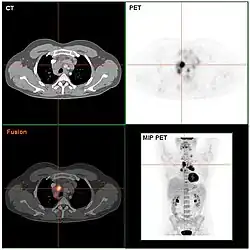

Tomografia komputerowa szyi. Kolorem czerwonym zaznaczono powiększone węzły chłonne

Badania obrazowe w chłoniaku Hodgkina pomagają ocenić zajęcia grup węzłów chłonnych i lokalizacji pozawęzłowych niedostępnych w badaniu fizykalnym[9]. Ocena zajęcia różnych grup węzłowych i lokalizacji pozawęzłowych pozwala na ocenę stopnia zaawansowania[89]. Podstawowym badaniem w ocenie zaawansowania chłoniaka Hodgkina jest tomografia komputerowa klatki piersiowej z lub bez oceny szyi, jamy brzusznej i miednicy[9]. U chorych z dużymi zmianami w śródpiersiu zaleca się wykonanie RTG klatki piersiowej[90]. Rezonans magnetyczny (MRI) znajduje zastosowanie głównie do oceny zmian w obrębie tkanek miękkich i zajęcia ośrodkowego układu nerwowego[9]. Również pozytonowa tomografia emisyjna (PET) może być użyta w celu oceny zaawansowania choroby, badanie wykazuje dużą czułość w wykrywaniu zajęcia szpiku i u chorych z nowo rozpoznaną chorobą badanych metodą PET nie jest konieczna biopsja szpiku[90].

Istnieją badania przemawiające za prognostycznym znaczeniem PET-TK po 2 cyklu leczenia[97].

PET-TK. Zaznaczony aktywnie metabolicznie węzeł chłonny śródpiersia

Ocena odpowiedzi na leczenie jest elementem strategii leczniczej i ma za zadanie ocenę skuteczności pierwszego etapu leczenia i dostosowanie intensywności dalszego leczenia po leczeniu wstępnym[182]. Ocena odpowiedzi na leczenie w stadium wczesnym jest przeprowadzana po zakończeniu chemioterapii przed radioterapią. W stadium zaawansowanym odpowiedź jest oceniana po 4 kursach chemioterapii[11][143]. W ocenie odpowiedzi na leczenie wykorzystuje się badanie fizykalne chorego, podstawowe badania laboratoryjne i tomografię komputerową lub PET-TK, gdy jest ono dostępne[143]. Obecnie stosuje się kryteria odpowiedzi zaproponowane przez Międzynarodową Grupę Roboczą w Lugano[11].